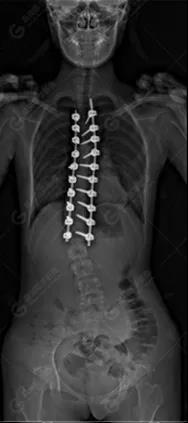

15歲女性,發(fā)現(xiàn)特發(fā)性脊柱側(cè)彎3年,于2019年1月23日來到廣東高尚醫(yī)學(xué)影像診斷中心行EOS檢查,2019年2月行手術(shù)治療后多次到中心行EOS復(fù)查。

2019-07-04

脊柱側(cè)彎最重要一個臨床參數(shù)是側(cè)彎角(Cobb角),目前臨床公認(rèn)的Cobb角>10 °診斷為脊柱側(cè)彎;如Cobb角進(jìn)行性持續(xù)性增加>40 °需要手術(shù)矯正治療。

本例患者胸椎右側(cè)彎,Cobb角(T6/T12)為47°,遂行手術(shù)矯正治療。術(shù)后多次隨訪的Cobb角(T10/L3)為12°-15°之間,較術(shù)前明顯縮小。